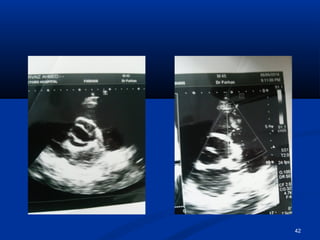

EEcchhooccaarrddiiooggrraapphhyy

42

 HHee hhaasslleeuuccooccyyttoossiiss,,  RRaaiisseedd CCRRPP  RRaaiisseedd LLDDHH  UURRIINNEE :: nneepphhrriittiicc ppiiccttuurree  PPlleeuurraall fflluuiidd:: ttrraannssuuddaattiivvee.. (( ttrraannssiieenntt))  BBlloooodd ccuullttuurree :: - vvee  HHCCVV:: ++vvee .. AAuuttooiimmmmuunnee sseerroollooggyy :: -vvee..  AAnnggiiooggrraapphhyy:: nnoorrmmaall  CCTT.. bbrraaiinn,, EECCHHOO,, aanndd DDoopppplleerr II sshhoowweedd yyoouu.. 50